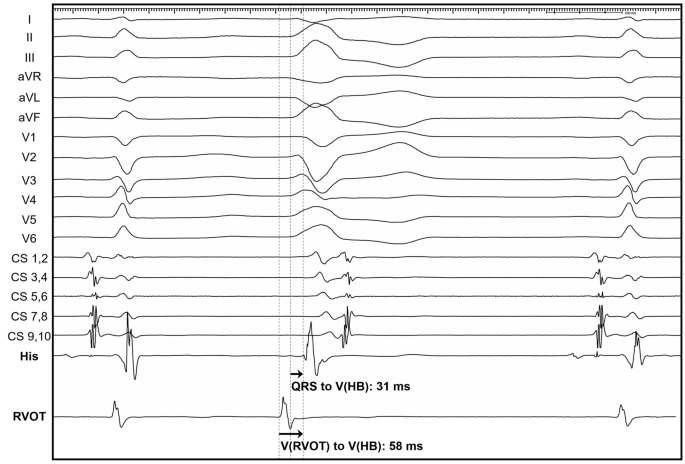

The 12-lead ECG and intracardiac electrogram recordings were retrospectively reviewed at a rate of 200 mm per second, and electrophysiological parameters were measured using the digital calipers of the Prucka Cardio Lab system. If intravenous isoproterenol was required to induce the clinical VA, measurements were performed under isoproterenol infusion. The QRS-V(HB) interval was measured from the onset of the QRS complex on a surface 12-lead ECG to the onset of the ventricular component of intracardiac His bundle electrograms during the clinical VA (Fig. 2). The onset of the QRS complex was defined as the earliest initial deflection from the isoelectric line on the 12-lead surface ECG. Additionally, the V(RVOT)-V(HB) interval was measured from the local ventricular signal on the mapping catheter placed in the RVOT region to the onset of the ventricular component of the intracardiac His bundle electrograms under fluoroscopic and electroanatomical guidance. To collect the local ventricular signals, the Lasso mapping catheter was advanced into the RVOT to the level of conus arteriosus. The cranio-caudal position of the mapping catheter was adjusted to the earliest set of endocardial activation times by visual estimation. While attempting to maintain the circular part of the catheter in a transverse position, local ventricular signals were recorded and the earliest local activation time in the RVOT (V(RVOT)) was obtained. All retrospective measurements were performed by two electrophysiologists. The inter-observer differences in measured parameter did not exceed 10 ms in any case, and the mean value of the measurements was used in the final analysis.

Representative measurements of V(RVOT)-V(HB) intervals (interval from the RVOT electrogram to the V signal in the His bundle electrogram) and QRS-V(HB) intervals (interval from the onset of the earliest QRS complex in 12-lead surface electrocardiogram to the V signal in the His bundle electrogram) in cases of ventricular arrhythmia originating from the RVOT